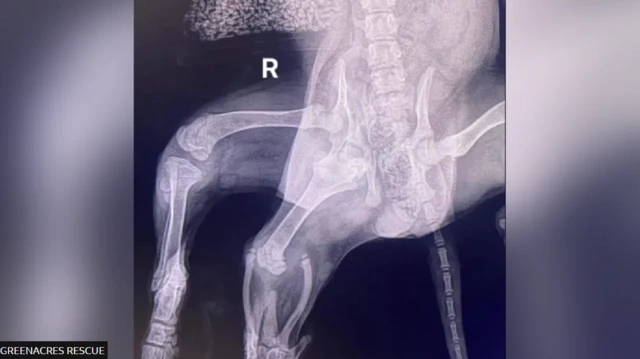

Аріель, шестилапій собаці, яку знайшли покинутою на парковці супермаркету, зробили операцію з видалення зайвих кінцівок.

"Ветеринар, який спочатку оглядав Аріель, зазначив, що окрім двох зайвих задніх лап у неї також є додаткова вульва", — сказав 42-річний чоловік.

Він додав, що комп’ютерна томографія, яка пізніше показала, що у неї лише одна нирка, збільшила складність необхідного медичного лікування.

"Через наявність двох тазостегнових суглобів з одного боку таз Аріель так і не сформувався належним чином. У результаті її звичайна задня права лапа практично не мала м’язового тонусу, тож існувала ймовірність, що її також доведеться ампутувати", - пояснив Майкі Лолор.